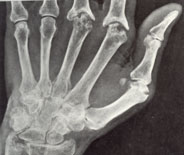

Αρθρώσεις που προσβάλλονται συχνότερα στην Ρευματοειδή αρθρίτιδα είναι: οι μικρές αρθρώσεις των χεριών ( εικόνα 5) (μετακαρποφαλλαγγικές, οι εγγύς φαλαγγοφαλαγγικές και οι καρποί).

![]() |

| εικόνα 5 | εικόνα 6 |

και των ποδιών (εικόνα 6) (μεταταρσοφαλαγγικές, οι εγγύς φαλαγγοφαλαγγικές και οι ποδοκνημικές), τα γόνατα, οι ώμοι και πιο σπάνια τα ισχία, οι αγκώνες και η σπονδυλική στήλη (εικόνα 7).